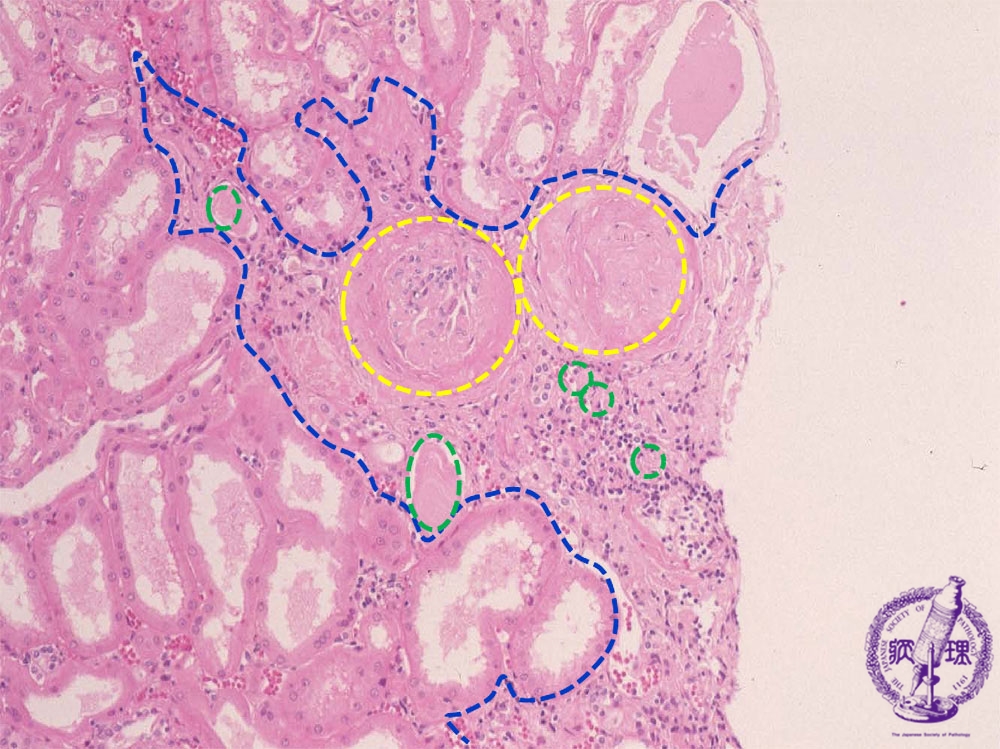

- 12.Kidney and Urinary System

- ★(10)Nephrosclerosis(benign nephrosclerosis)

Microscopic findings (HE, middle power view): The wedge-shaped compressed region (blue dotted line) shows sclerosis of the glomeruli (yellow dotted lines) and atrophy of the tubules (green dotted lines).